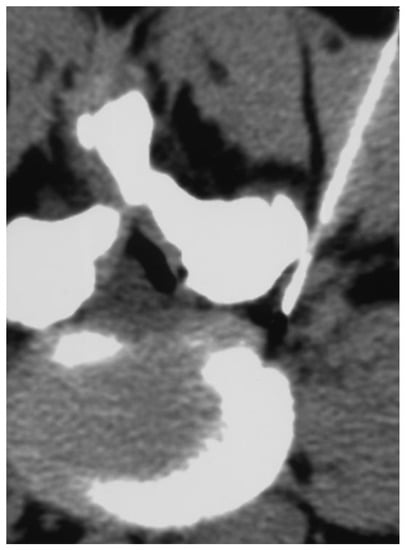

2.1. Infiltration Technique